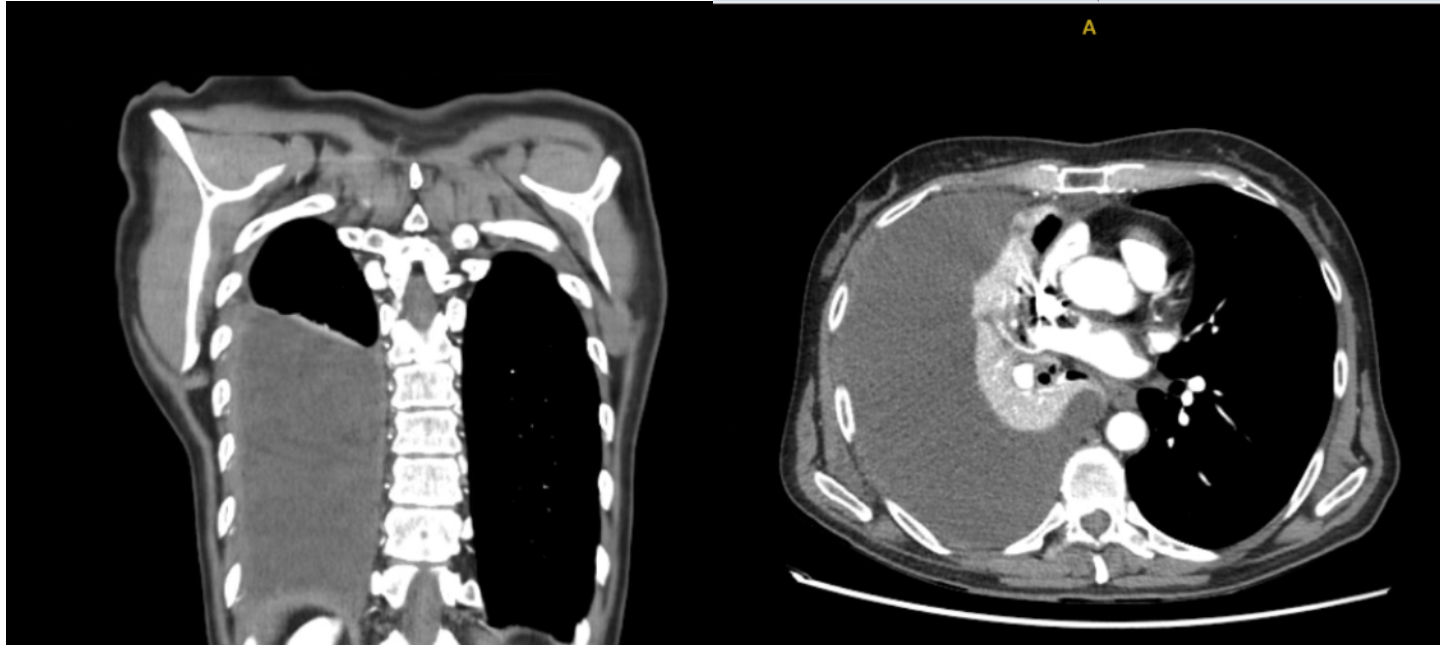

En urgencias hospitalarias: Dímero D 1400 , sin leucocitosis, Radiografía de tórax derrame pleural derecho, Angiografía pulmonar: descarta TEP. Moderado/severo derrame pleural derecho con atelectasia pasiva.

Realizamos Ecografía clínica pulmonar: imagen anecoica con septos finos y signo de la medusa compatible con derrame pleural tabicado con atelectasia en base derecha de aproximadamente 1150 ml por cuantificación de Goecke 2, en ápex líneas B finas. Campo pulmonar izquierdo líneas A.